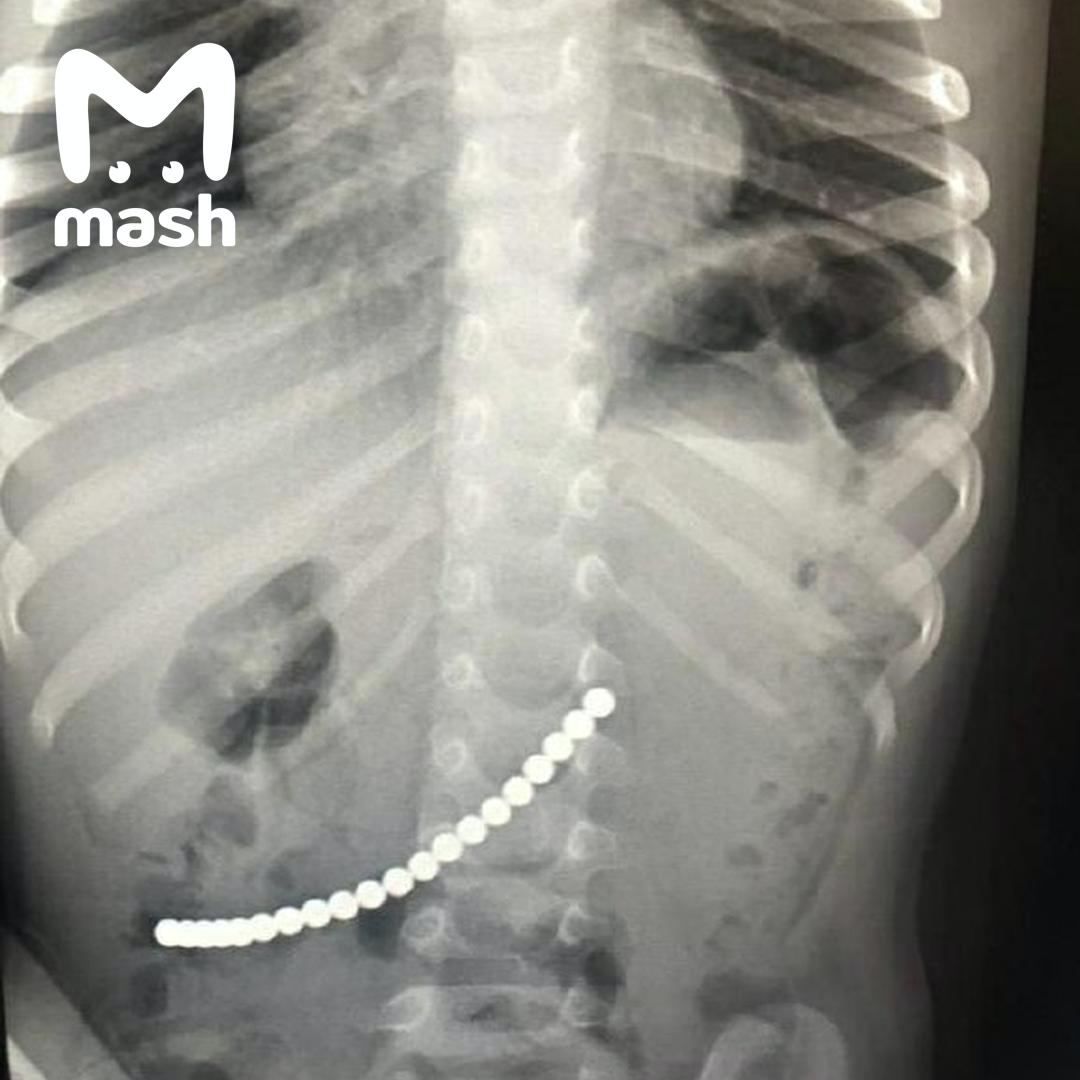

Магнитные шарики на рентгене: Интересные находки

Раздел: Картинки на заметку